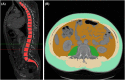

Methods: Preoperative CT scans of 137 patients who received LVADs between 2015 and 2020 were retrospectively analysed using an artificial intelligence (AI)-powered automated software tool based on a convolutional neural network, U-net, developed for image segmentation (Visage Version 7.1, Visage Imaging GmbH, Berlin, Germany). Assessment of body composition included visceral and subcutaneous adipose tissue areas (VAT and SAT), psoas and total abdominal muscle areas and sarcopenia (defined by lumbar skeletal muscle indexes). The body composition parameters were correlated with postoperative major complication rates, survival and postoperative 6-min walk distance (6MWD) and quality of life (QoL).